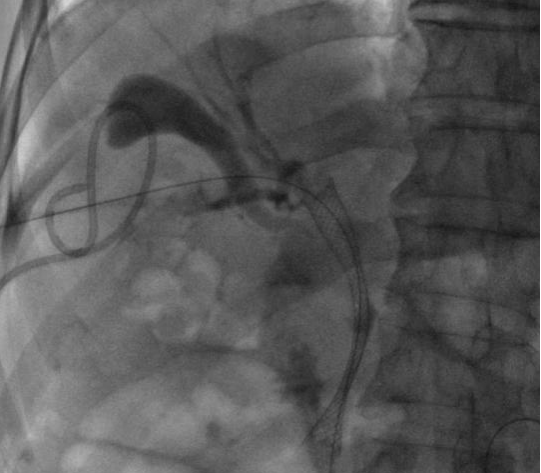

ERCP(內(nèi)鏡逆行胰膽管造影術(shù))是膽胰疾病精準(zhǔn)內(nèi)鏡診療技術(shù),具有不開(kāi)腹、風(fēng)險(xiǎn)小、創(chuàng)傷小、恢復(fù)快、住院時(shí)間大大縮短的優(yōu)點(diǎn),尤其是對(duì)年齡大、體弱多病的患者尤為適宜。ERCP主要運(yùn)用于膽總管結(jié)石的取出,以及在經(jīng)口膽道子鏡的輔助下完成肝內(nèi)膽管結(jié)石的取出。

0b4174cdbf1f4e508687f388367c9ca6.Jpeg

bc72d6558d394d8ea787e762f054a7c5.Jpeg74bcac877ae44a9da8e58dab53d178ee.Jpeg75e90c629e6545de9ee764d5e15bc91e.JpegERCP取出膽總管結(jié)石

對(duì)于無(wú)法手術(shù)切除的膽管或胰腺惡性腫瘤導(dǎo)致的梗阻性黃疸,可以進(jìn)行ERCP下膽道支架植入,以緩解梗阻性黃疸癥狀,提高患者生活質(zhì)量。通過(guò)光動(dòng)力、射頻消融等治療,還可以控制腫瘤的生長(zhǎng),提高膽道支架的通暢期,延長(zhǎng)患者生存時(shí)間。